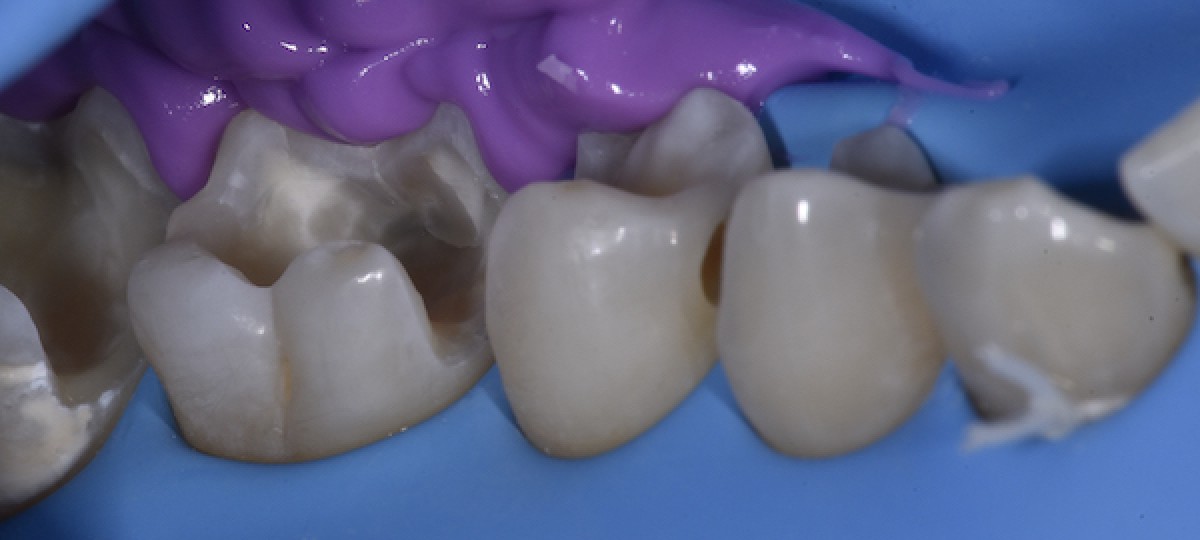

Mesio-lingual cusp stamped (photo taken during index removal) (Fig.9)